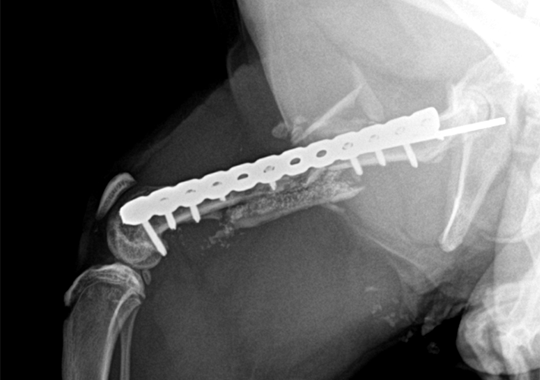

대퇴골 복합골절 및 천장골분리골절 전

대퇴골 복합골절 및 천장골분리골절 후

타원 실패 수술 후 2차 수술 전

타원 실패 수술 후 2차 수술 후